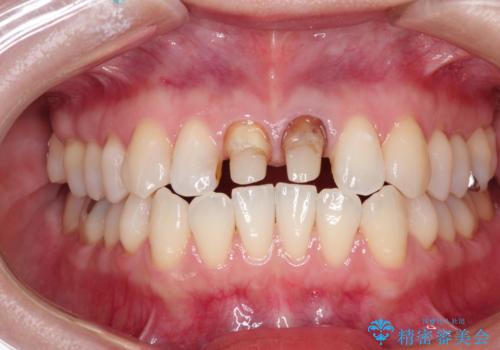

前歯の根元が黒い オールセラミッククラウンの装着による改善

- 10年前ほどに前歯に装着されたセラミックの根元の方が黒くなってきたのが気になるとのことで来院されました。

上顎の前歯の歯茎が下がり、ご自身の歯が露出している状態でした。

金属の土台をファイバーコアに交換後、オールセラミッククラウンを装着する計画としました。